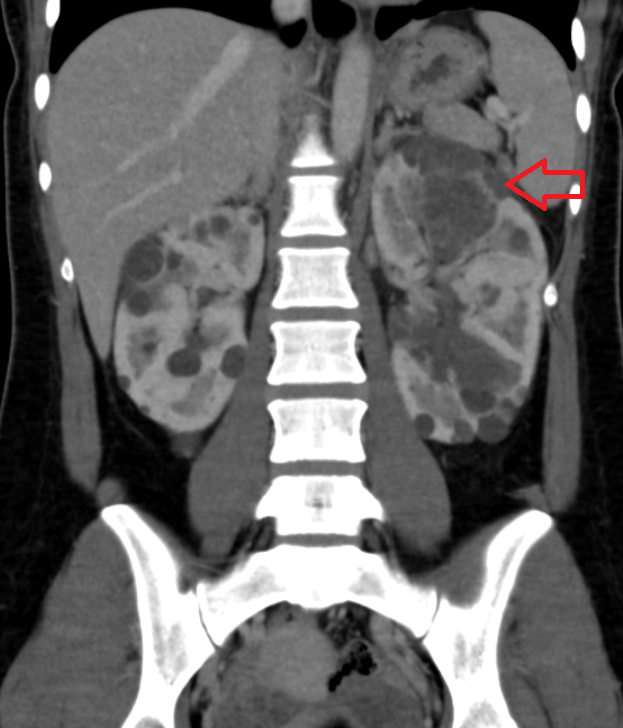

• 혈액검사: CRP 18↑, 복부CT검사: 급성신우신염 혈액검사: CRP 18↑, 복부CT검사: 급성신우신염

• 신장의 실질은 조영제가 들어가게 되면 하얗게 잘 표시가 되어야 하는데 까맣게 표시간 되지 않는 부분이 보임(신장 내 염증) 신장의 실질은 조영제가 들어가게 되면 하얗게 잘 표시가 되어야 하는데 까맣게 표시간 되지 않는 부분이 보임(신장 내 염증)